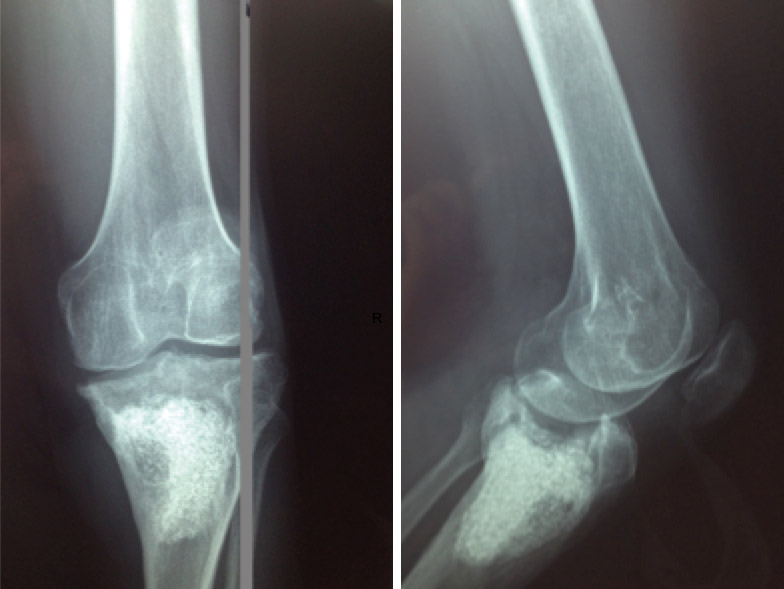

El paciente no presenta mejoría, por lo que un mes después se decide realizar una resonancia magnética de la rodilla, donde se observa abundante derrame y una región de secuestro óseo que ocupa la epífisis y la metáfisis proximal de tibia (Figura 1).